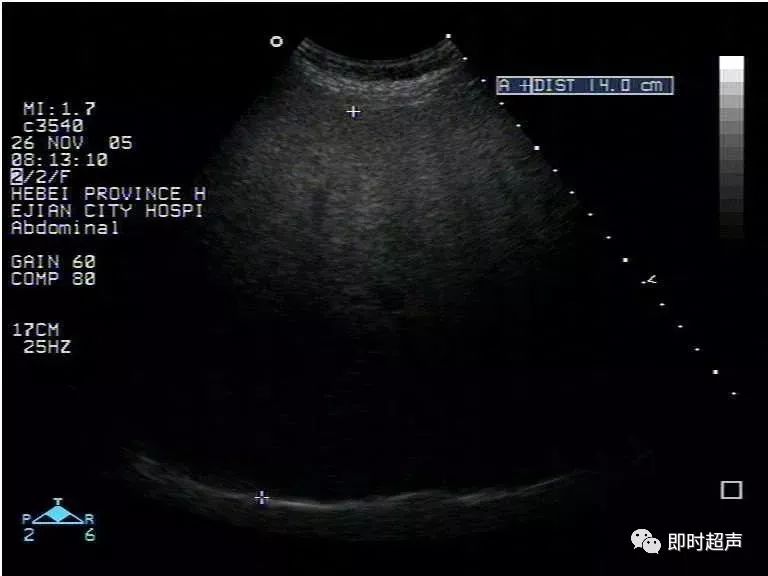

超声表现:

1、肝实质回声细密增强,呈云雾状,后方回声衰减。

2、肝内管道结构显示欠清。

3、肝肾对比阳性,正常情况下肝脏回声略高于肾实质回声,脂肪肝时肝脏回声明显增强。

4、肝脏增大,形态饱满,边缘变钝。

重度:后方回声衰减明显,后方肝组织显示不清,膈肌显示不清。